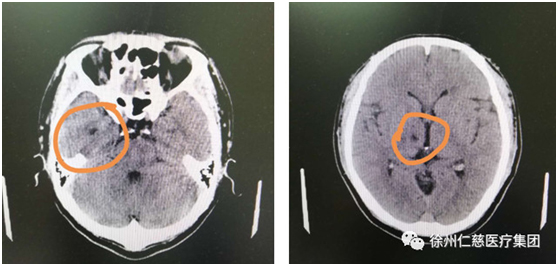

在徐主任的建議下,張師傅做了頭顱CT,檢查提示:兩基地節(jié)區(qū)、右側(cè)丘腦腔隙性腦梗塞,副鼻竇炎,腦干腔隙性梗塞不能排除。好在徐曉欣主任經(jīng)驗(yàn)豐富,迅速聯(lián)系將張師傅轉(zhuǎn)入內(nèi)科,張師傅的腦梗得以及時治療。